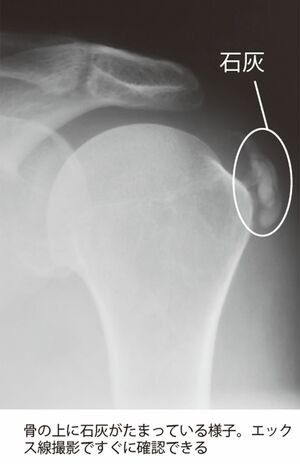

経験したことのないような痛みに耐えながら朝になるのを待って、最寄りの整形外科を受診。エックス線検査の結果、医師から告げられたのは「肩に“石”ができていますね」という、思いもよらないものだった。

A子さんを襲ったこの病気、正確には「石灰沈着性腱板(けんばん)炎」という。初めて聞くという人も多いかもしれない。A子さんはその病名に思わず身構えたという。

「肩の筋肉が上腕の骨にくっつくところを“腱板”といいます。この腱板の中や表面に石灰がたまり、それが強い炎症を起こして激烈な痛みを起こす病気です。